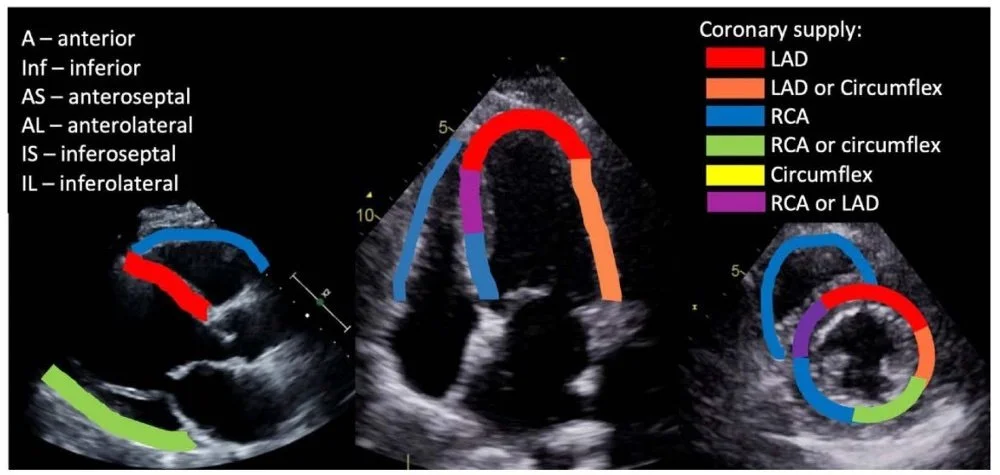

This image demonstrates a regional wall motion abnormality (RWMA) in the left anterior descending artery (LAD) distribution (Figure 1). This RWMA can be visualized in multiple windows (PLAX, PSAX, A4C) but is best interpreted at multiple tissue levels of the PSAX view.

Figure 1. Coronary artery vascular distribution on FoCUS exam (Image from: https://asra.com/news-publications/asra-newsletter/newsletter-item/asra-news/2021/08/02/pocus-spotlight-focused-cardiac-ultrasonography)